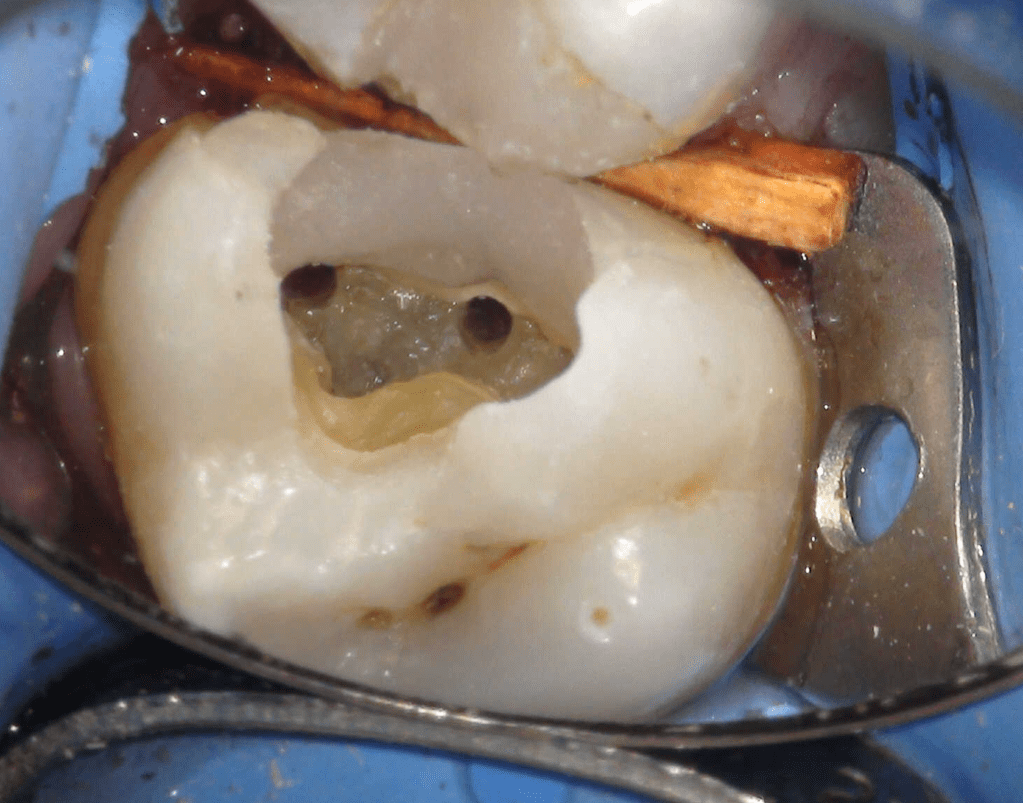

Pulpotomía biodentine + reco preendio